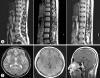

We report a case of intracranial dissemination developing approximately 4 months after partial removal of a spinal cord anplastic astrocytoma in a 22-year-old male. He presented with paraplegia on initial admission at a local hospital. Spinal magnetic resonance (MR) images disclosed multiple intramedullary lesions at the T3-11. The tumor was partially removed. The final histologic diagnosis was anaplastic astrocytoma. Four months after the operation, he was admitted with the symptoms of headache and deterioration of consciousness. MR images showed enhanced lesions in the anterior horn of the left lateral ventricle, and septum pellucidum. He underwent computed tomography-guided stereotactic biopsy and histological appearance was consistent with anaplastic astrocytoma. The clinical course indicates that the tumor originated in the spinal cord and extended into the subarachnoid space, first the spinal canal and later intracranial.